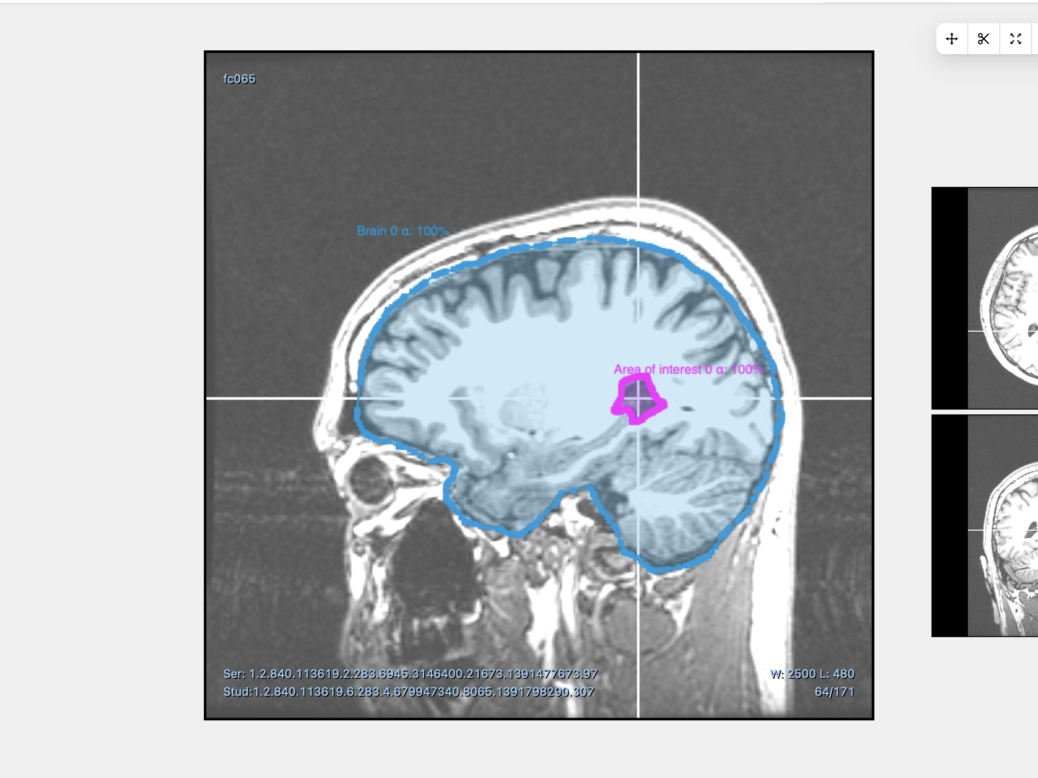

The AI platform can automatically classify, detect, segment and track objects in images and videos. The solution the Encord CTO has helped develop also enables users to leverage AI to scan X-rays and CT scans. To date, the company has raised $17m, most recently through a $12.5m Series A round in October 2021.